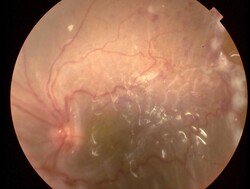

Imágenes

Figura 1. Desprendimiento de retina total con proliferación vítreo retinal y su imagen luego de vitrectomía y aceite de silicón.